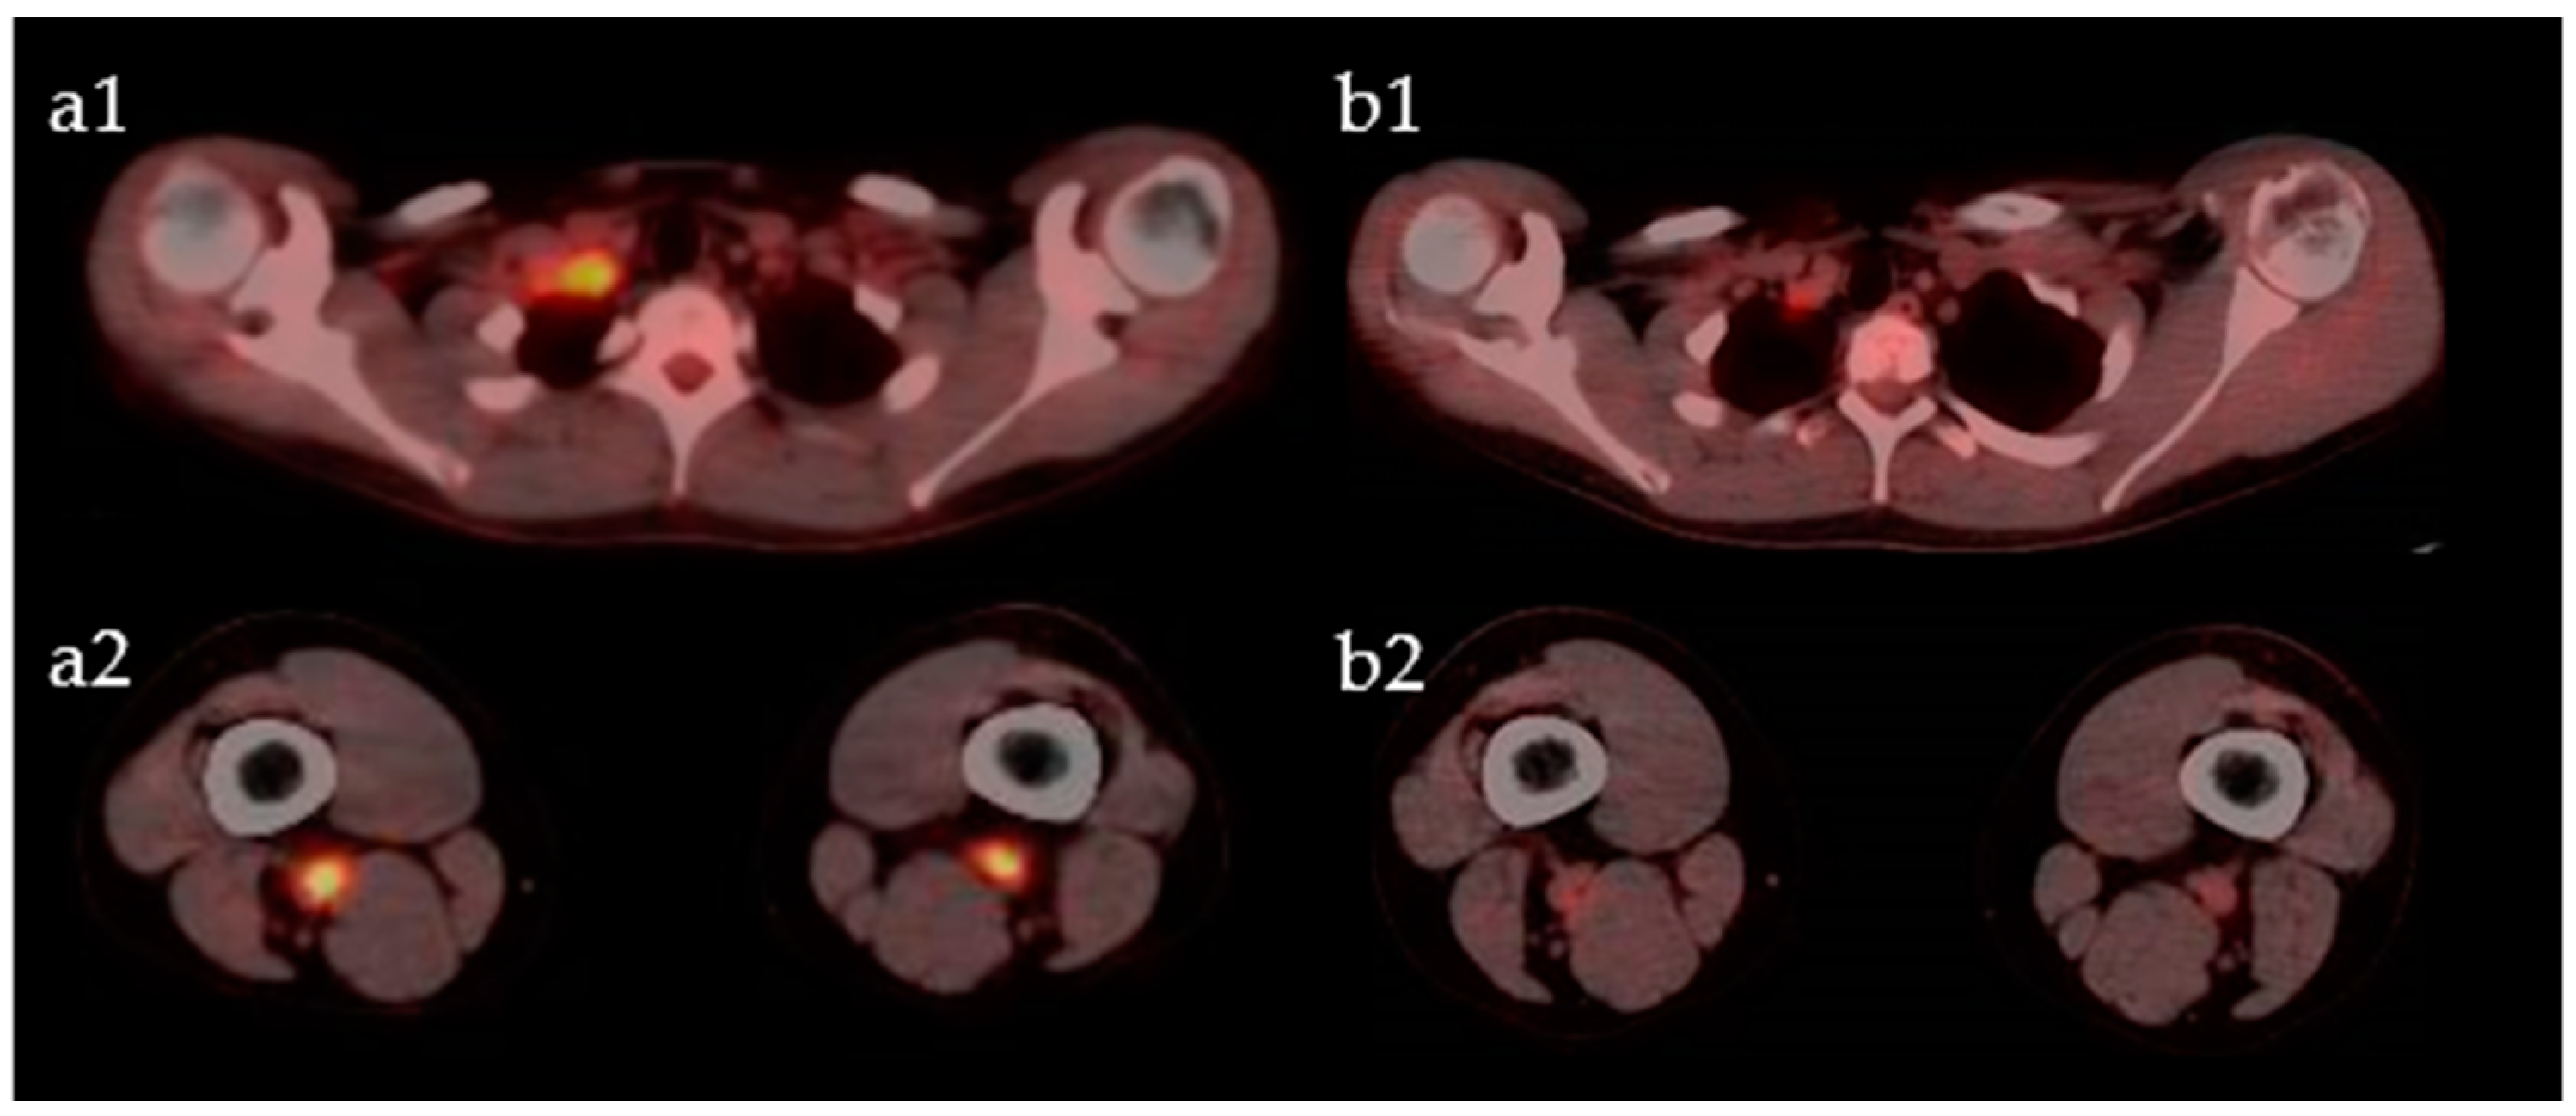

2. Case Presentation